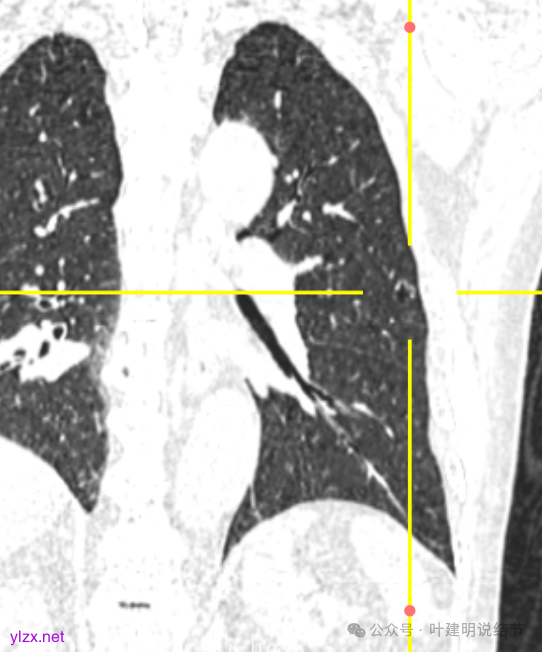

冠状位见病灶囊壁不均,表面不光滑,囊腔内壁也不太平整。

矢状位见病灶囊壁有结节状高密度。